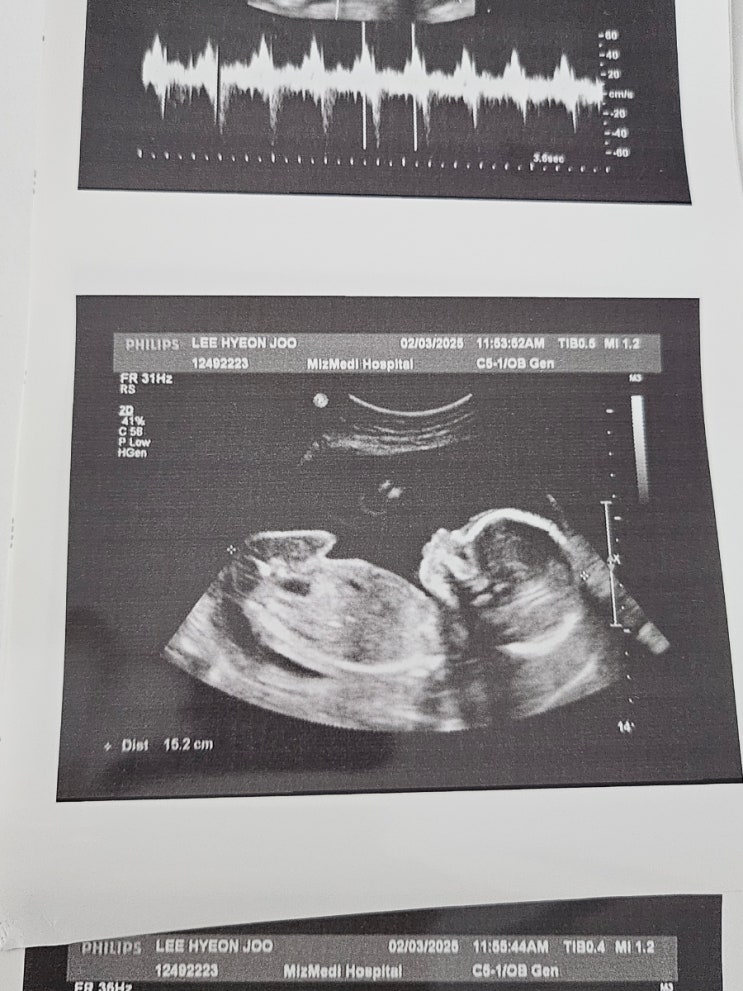

임신 25주차 | 미즈메디 임당검사, 입체초음파 후기

#임신25주차 #입체초음파 #임당검사후기 미즈메디 임신성당뇨(임당) 검사 나도 드디어 임당검사를 할때가 ...

임신 20주차 | 강서미즈메디 중기정밀초음파

임신 20주 6일차 중기정밀초음파 후기 1월에 내 생일도 있고, 설 연휴도 있고 회사도 1년중에 젤 바쁜달이...